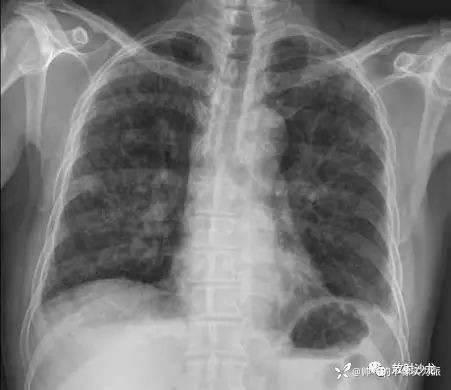

胸部平片见图1。胸部CT扫描显示多发结节、双侧气腔实变和磨玻璃征(图2),多发结节都分布在淋巴组织周围。腹部CT平扫显示胰头处有一个直径2 cm 的低密度团块阴影(图3)。对患者行气管镜检查以除外恶性疾病或结核,术中未见支气管内病变。对支气管镜获取的样本进行了细胞学检测、抗酸染色和TB聚合酶链反应,结果均为阴性;支气管肺泡灌洗液培养也为阴性。多重聚合酶联反应未检测到A 型和B 型流感病毒、1~3型副流感病毒、呼吸道合胞病毒、腺病毒、鼻病毒以及间质肺病毒。

图1 胸片显示两肺多发边界不清的结节影